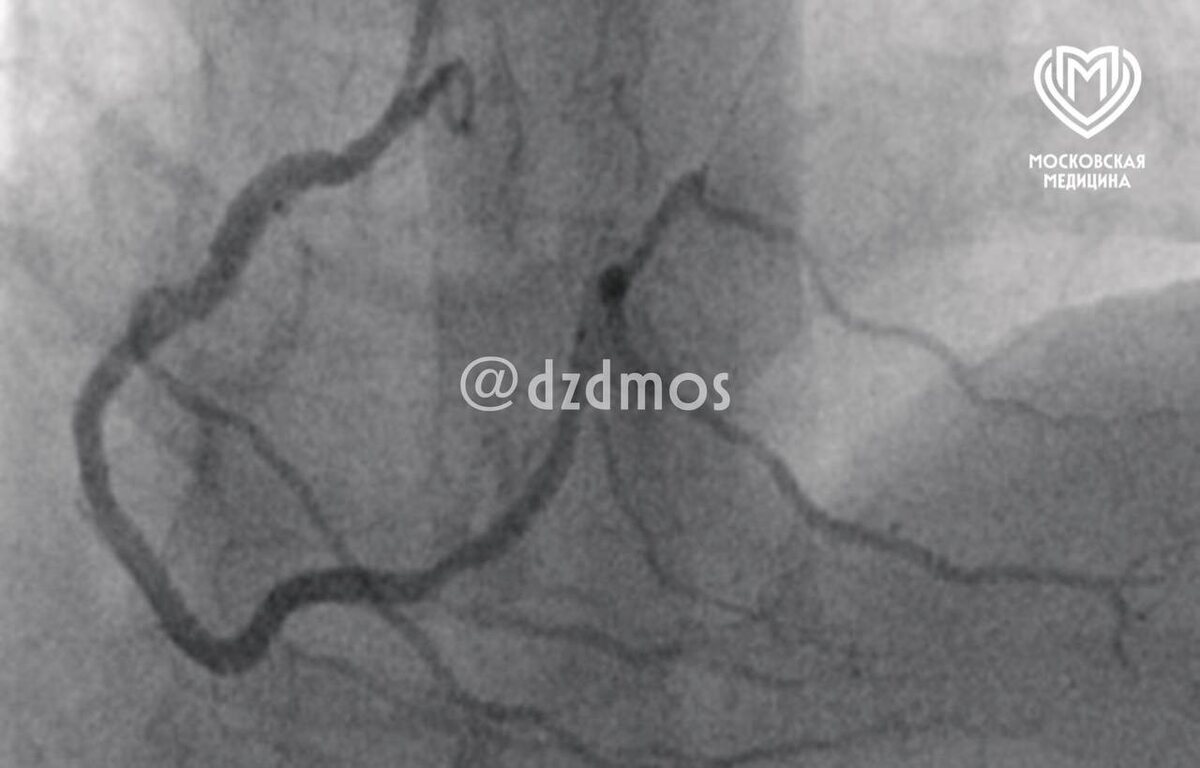

Свинина довела москвича до инфаркта. Сразу после еды мужчину госпитализировали с кардиогенным шоком. Оказалось, что мясо вызвало у него аллергию, которая раньше проявлялась только крапивницей. Пациента вылечили и отпустили домой. Это редкий случай синдрома Коуниса первого типа, когда обычная аллергическая реакция провоцирует опасные нарушения в работе сердца, объяснили в столичном Депздраве. ⭕️ Подписаться | Мы в MAX | Буст